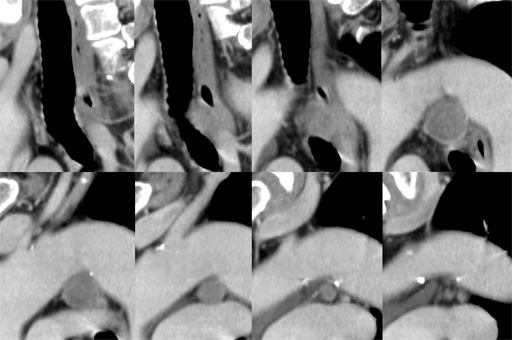

(sagittal image) 図6 胸部CT 肺野条件

図6 胸部CT 肺野条件 図7 MRI T1WI (in phase)

図7 MRI T1WI (in phase) 図8 MRI T1WI (out of phase)

図8 MRI T1WI (out of phase) 図9 MRI T2WI

図9 MRI T2WI 図10 MRI fat sat T2WI

図10 MRI fat sat T2WI 図11 MRI fat sat T1WI

図11 MRI fat sat T1WI

(dynamic study) 図12 DWI (b=500), ADC map

図12 DWI (b=500), ADC map